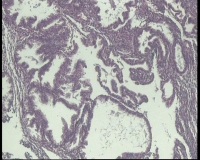

| 图片: | |

- 急!请老师看看34岁子宫内膜

| 性别 | 女 | 年龄 | 34岁 | 临床诊断 | 子宫内膜息肉? |

| 一般病史 | 末次月经:11月20日,近两个月无诱因性生活有阴道少许血性分泌物 | ||||

| 标本名称 | 宫内容物 | ||||

| 大体所见 | 膜样碎组织3.0厘米 | ||||